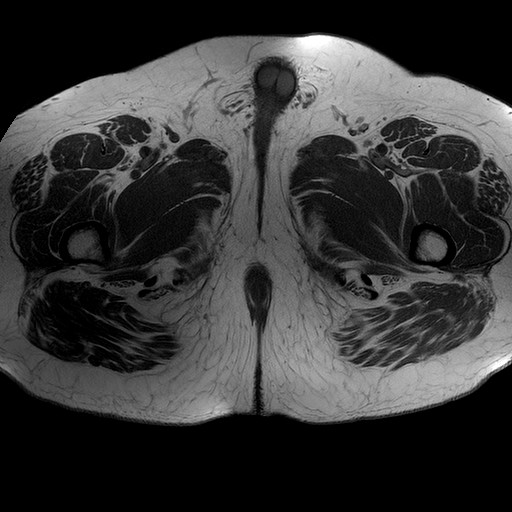

Esami: RMN BACINO

T1W_TSE

Evidenti e simmetriche alterazioni osteofitosiche in regione coxo femorale con riduzione delle rime articolari. Degenerazione completa del cercine glenoideo. Non attuali segni di versamento articolare. Non segni di edema osseo che escludono attuale algodistrofia od osteonecrosi. Lieve e simmetrica riduzione del trofismo della muscolatura glutea.